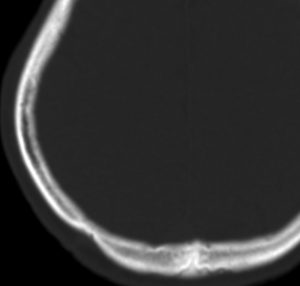

CTで典型的な頭蓋骨の打ち抜き像 punched out lesion が左頭頂骨にあります。これだけでLCHと診断がつくような画像です。

- 上の写真は,子供の右の頭頂骨にできたLCHで,頭部病変では最も多く見られるタイプです

- 頭蓋骨が丸く抜けるように破壊されるのでpunched out lesionと表現されます

- 頭蓋骨欠損がそれほど大きくないものは様子を見ます

- 自然に消失して治ってしまうことも多いです

- 単臓器単発型は無治療で経過をみるというのもよいでしょう